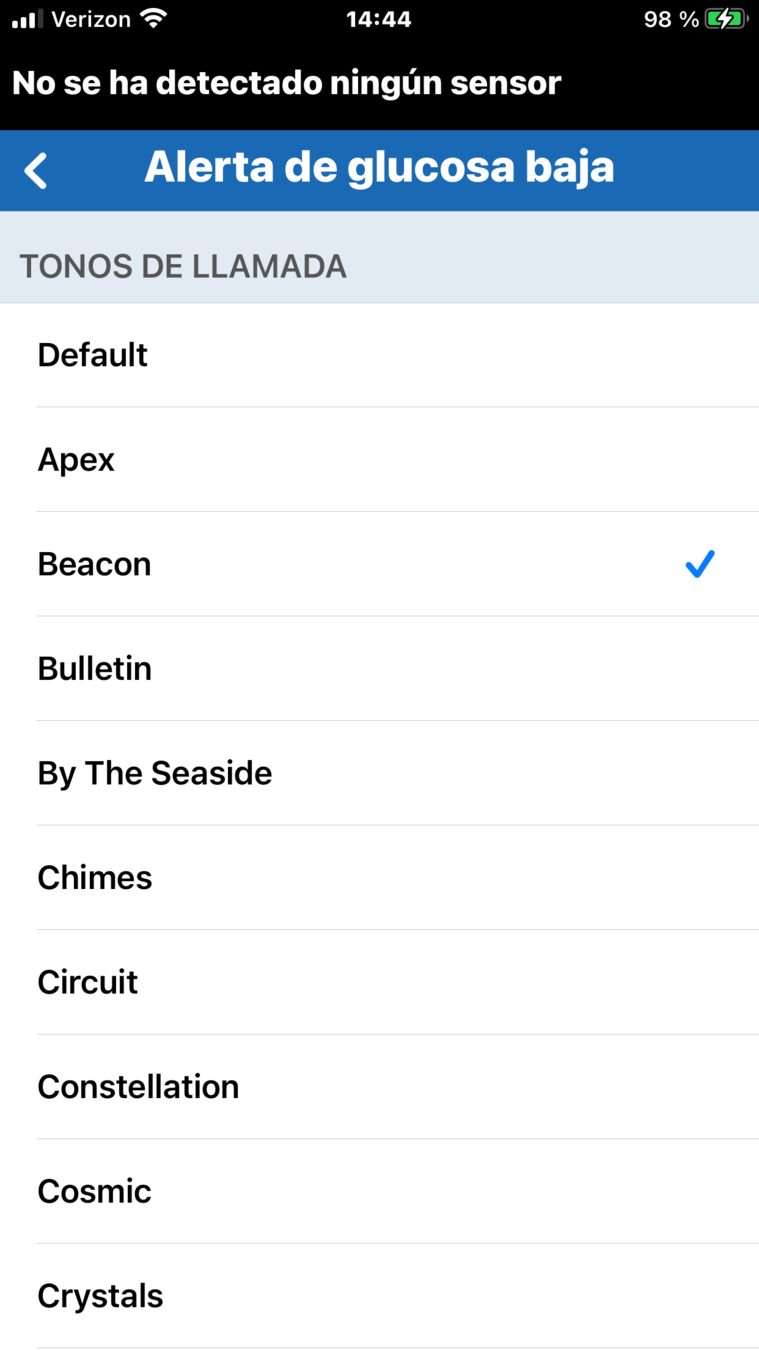

En la pantalla Configuración de sonido,

puede tocar el nombre de una alerta para abrir un menú de tonos que le permite establecer

un sonido especial para esa alerta concreta.

CONFIGURACIÓN DE SONIDO PERSONALIZADA

Por ejemplo, para cambiar el sonido de alerta de glucosa baja, toque el nombre del tono para escuchar cómo suena y decidirse.

CONFIGURACIÓN DE SONIDO PERSONALIZADA

En la pantalla Configuración de sonido, puede tocar el nombre de una alerta para abrir un menú de tonos que le permite establecer un sonido especial para esa alerta concreta.

CONFIGURACIÓN DE SONIDO PERSONALIZADA

Puede cambiar su elección tocando el nombre de otro tono.

Por ejemplo, para cambiar el sonido de alerta de glucosa baja, toque el nombre del tono para escuchar cómo suena y decidirse.

En la pantalla Configuración de sonido, puede tocar el nombre de una alerta para abrir un menú de tonos que le permite establecer un sonido especial para esa alerta concreta.